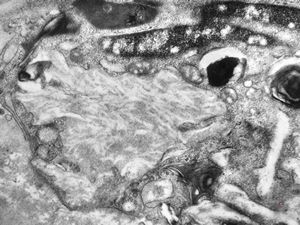

M,3y. | globoid leukodystrophy of Krabbe - n.suralis